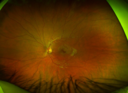

13 year old who was hit in the right eye with a softball about 2 years ago. Pain but no vision loss then. Got "blurry" OD about 5-6 months ago VA OD: Dcc20/40-2 NccJ2 VA OS: Dcc20/20

Choroidal Osteoma 13 Year Old565 views13 year old with 6 months of vision loss right eye and vision of 20/4000000